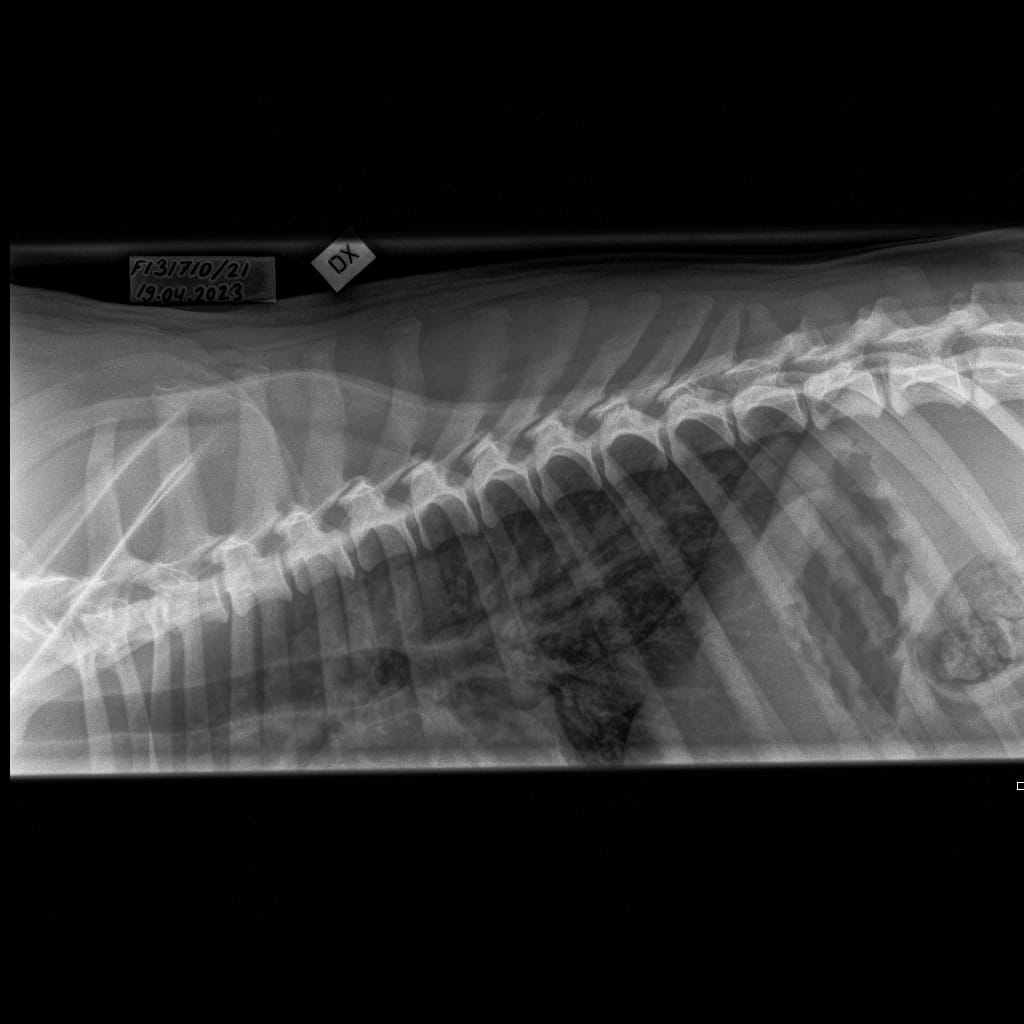

| Name | ID | Birth weigth | Ridge | Height | Weight | Bite | Hips | Elbows | Shoulders | Spine | MH | Other |

|---|---|---|---|---|---|---|---|---|---|---|---|---|

| Lumottu Uljas Iivonpoika ft. Finnridge | Blue ♂︎ | 505 g | Correct | TBA | TBA | TBA | B/B | 0/0 | Unaffected/Unaffected | LTV1, SP0, VA1 | MH, gunshot proof | Low-grade MCT removed 06/2024 |

| Lumottu Aatos Iivonpoika ft. Finnridge | Turqoise ♂︎ | 530 g | Correct | TBA | TBA | TBA | B/B | 0/0 | Unaffected/Unaffected | LTV2, SP0, VA0 | MH, gunshot proof | |

| Lumottu Martta Iivontytär ft. Finnridge | Lime ♀︎ | 525 g | Correct | TBA | TBA | TBA | A/A | Xray: 0/0 CT: 3/1 | Unaffected/Open to interpretation | LTV0, SP0, VA0 | MH, unfamiliar to gunshot | |

| Lumottu Armas Iivonpoika ft. Finnridge | Orange ♂︎ | 440 g | Correct | TBA | TBA | TBA | A/A | 0/0 | Unaffected/Unaffected | LTV0, SP0, VA0 | MH, unfamiliar to gunshot | |

| Lumottu Aulis Iivonpoika ft. Finnridge | Aqua ♂︎ | 440 g | Correct | TBA | TBA | TBA | B/B | 1/1 | Unaffected/Unaffected | LTV1, SP0, VA0 | Handler interrupted | |

| Lumottu Irma Iivontytär ft. Finnridge | Pink ♀︎ | 550 g | Correct | TBA | TBA | TBA | C/B (low sockets) | 0/0 | Unaffected/Unaffected | LTV0, SP0, VA0 | Spring 2024 | |

| Lumottu Sirkka Iivontytär ft. Finnridge | No collar ♀︎ | 390 g | Ridgeless | TBA | TBA | TBA | A/A | 0/0 | Unaffected/Unaffected | LTV1, SP0, VA0 |